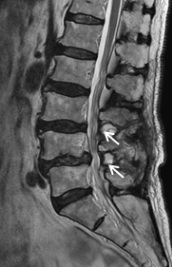

第2腰椎と第3腰椎に高度の骨粗鬆性椎体骨折を認めます。連鎖した骨折椎体は原型を失い扁平化・楔状化を来し、強い腰曲がり・脊柱後弯を呈しています。強い腰痛と体幹バランス不良のため歩行不能でした。MRIでは神経が強く圧迫されているのが分かります。

圧潰して原型を失った第2腰椎と第3腰椎に対して前方進入椎体置換術を行い、後方から広範囲矯正固定術を行っています。亀背は残りましたが、腰痛・神経症状は大幅に改善して杖で歩くことができるようになりました。